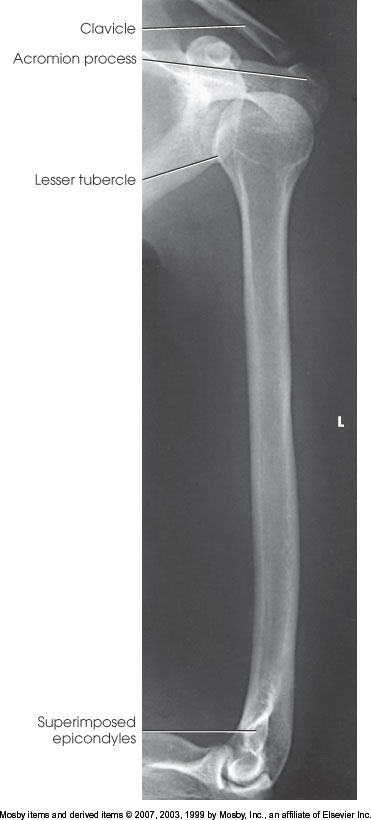

Lateral Humerus

What position is demonstrated?